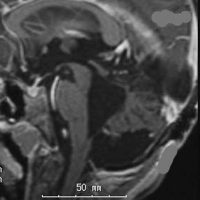

同じような小児例です

右側は手術直後のFLAIR像です。小児ですから大きなのう胞はすぐに潰れて小脳がもどります。白質損傷もなく腫瘍は摘出できています。